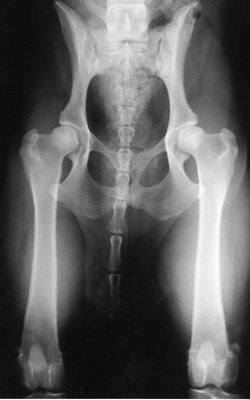

Die Untersuchung beinhaltet drei verschiedenen Röntgenaufnahmen. Im Folgenden finden Sie Beispiele dreier Aufnahmen eines 15 Monate alten Labrador Retrievers.